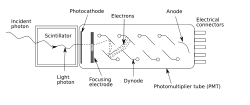

Гамма-камера — сцинтилляционная камера, регистрирующая гамма-излучение. В сцинтилляторе гамма-камеры поглощённые или рассеянные гамма-кванты преобразуются в фотоны видимого излучения, причём количество излученных фотонов пропорционально поглощённой в сцинтилляторе энергии гамма-кванта. Фотоумножители преобразуют световую вспышку в сцинтилляторе в импульс тока, который регистрируется спектрометрической аппаратурой. Амплитуда импульса пропорциональна поглощённой в сцинтилляторе энергии гамма-кванта, поэтому возможно отделение вспышек от гамма-квантов с энергией, характерной для используемого маркера, от фона. Применение сборки фотоумножителей позволяет осуществить восстановление координат вспышки и, таким образом, измерить пространственное распределение маркера в теле пациента.

Сцинтилляционная гамма-камера — медицинский прибор для радиоизотопной диагностики. Представляет собой многоканальный коллиматор; на выходе каждого из каналов установлены ФЭУ (фотоэлектронные умножители - высокочувствительные детекторы фотонов), сигналы которых обрабатывают на компьютере. После введения в организм препарата, меченного радиоактивными изотопами, с помощью гамма-камеры можно получить на экране картину распределения препарата в исследуемом органе, а также наблюдать в динамике процесс его выведения.

Гамма-камера состоит из детектора (большого сцинтилляционного кристалла, обычно из NaJ(Tl)[уточнить]), световода, набора ФЭУ, сменных свинцовых многоканальных коллиматоров и блока аналоговых электронных устройств, обеспечивающих определение координат и амплитуд сигналов, компьютера и консоли оператора.

Система для диагностики всего тела требует наличия подвижного детектора, который проходит вдоль тела пациента, либо подвижного стола, который движется под неподвижным детектором. Во избежание погрешностей, привносимых излучением от посторонних источников, детектор помещают в защитный кожух, выполненный из свинца или его сплавов. Пространство, с которого на детектор поступает излучение, ограничивается и формируется сменными диафрагмами (коллиматорами) из свинца, которые имеют разную форму в зависимости от типа исследования. Толщина свинцовой защиты зависит от применяемых изотопов. Излучение должно ослабляться защитой в 1000 раз[уточнить]. Для излучения с энергией 140 кэВ достаточно свинцовой защиты толщиной 10 мм, а для энергии 500 кэВ необходимо 50 мм.